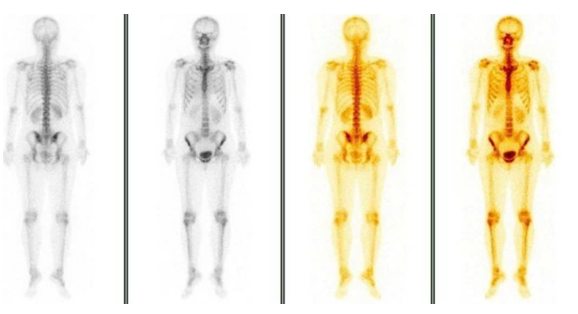

– Xạ hình xương (Tháng 04/2025): chưa phát hiện bất thường

Hình 7: Xạ hình xương chưa phát hiện bất thường